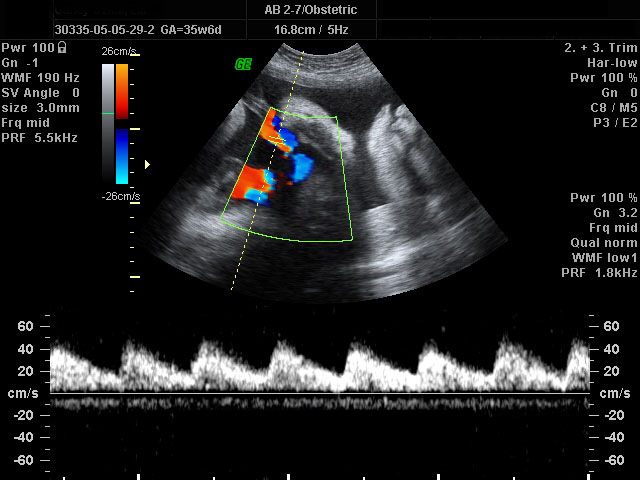

Doppler genel anlamda ultrason altında incelenen damar yatağının kan akımını ve normal dışı bir dire ...